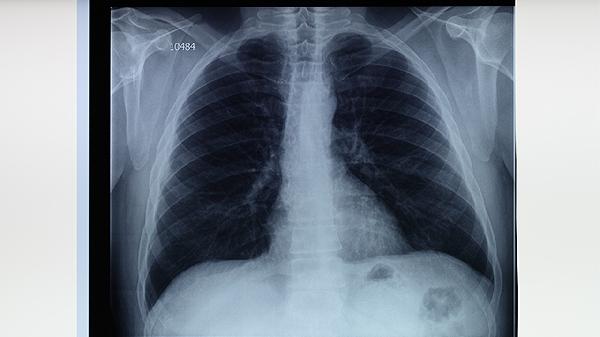

胸部X線可發(fā)現(xiàn)典型的上葉尖后段浸潤(rùn)影、空洞或鈣化灶,CT能更清晰顯示早期微小病灶和淋巴結(jié)腫大?;顒?dòng)性肺結(jié)核常見(jiàn)表現(xiàn)為多形性陰影,陳舊性結(jié)核則以纖維條索影為主。影像學(xué)異常需結(jié)合其他檢查綜合判斷。